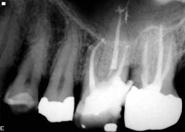

Parodontite usoare

sângerare gingivala mai pronuntata

gingia începe sa se detaseze fata de dinte

halena

pungi parodontale de 3-4 mm

demineralizare osoasa halistereza